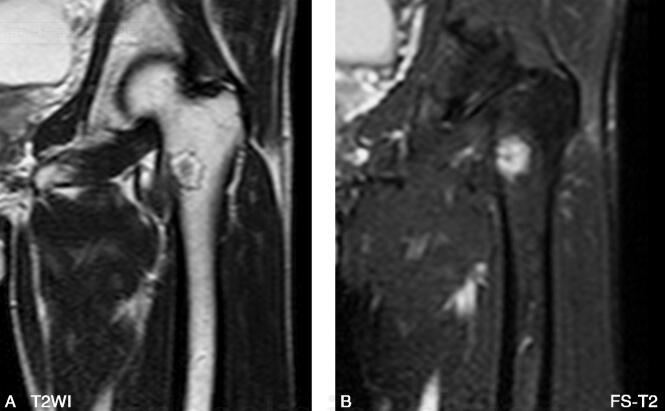

男,53岁,左髋部不适感1年余(图1~3)。

图3 MR:左侧粗隆间可见类圆形异常信号改变,边缘环形低信号,其内信号

(三)MRI

MRI能通过任意断面显示病灶和髓腔分隔,更清晰显示周围软组织受累的情况,而且能通过病灶信号特点评价其病理成分。病灶T1WI多呈低至等信号,而T2WI信号变化较大,病理结果显示,T2WI呈现高信号的病灶比低信号者有更少的骨小梁、更少的细胞成分及胶原纤维。由于骨纤在病变的不同阶段可有不同的病理改变,如病灶内存在较多囊变及坏死液化,则在T1WI呈低信号,在T2WI呈高信号。而病灶内的出血、软骨岛、残存的骨髓脂肪等成分,则在T1WI和T2WI均呈高信号。病灶内的钙化和周边的硬化在T1WI和T2WI均呈明显的低信号。增强扫描病灶可见不同程度的强化,这是因为在病灶的中心有较多小血管而且周边有大量的血窦,同时表明病灶代谢活跃。